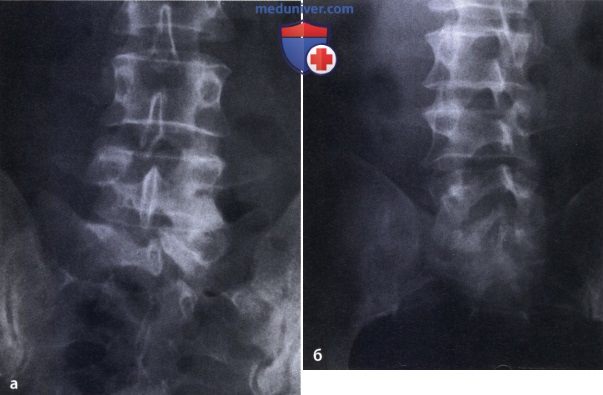

Рентген шейных позвонков при спина бифида

Раздел: Фотозарисовки